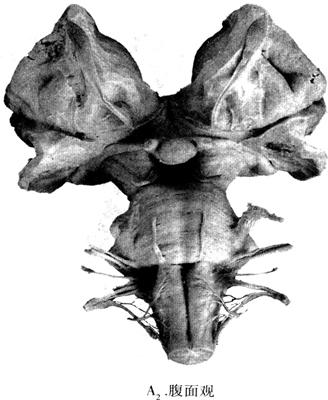

图12-26 脑干的外形(A2)

脑干的腹面借表面的桥延沟和脑桥上缘为界,从下往上依次分为延髓、脑桥和中脑(图12-26A)。延髓部中线的两侧各有一隆起,称为锥体(pyramid),其深面有锥体束,下方为锥体交叉(decussation of pyramid);锥体外侧有橄榄体(olive),以及位于橄榄体背侧的Ⅸ、X、Ⅺ对脑神经,腹侧的Ⅶ对脑神经;桥延沟由内往外有Ⅵ、Ⅶ、Ⅷ对脑神经。脑桥腹面的正中有上下走行的基底动脉沟(basilar sulcus),有同名动脉通过,其外侧可见V对脑神经,该神经是脑桥基底部与脑桥臂表面之界标。在中脑可见由大量下行传导束所形成的粗大隆起称大脑脚,和两侧大脑脚之间形成的脚间窝,内有Ⅲ对脑神经走出。